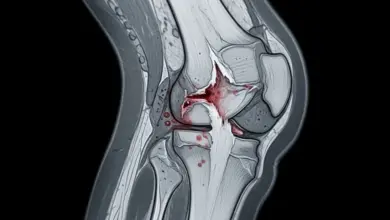

Boa parte do sucesso está no planejamento. Radiografias panorâmicas com carga, estudo do eixo mecânico, análise do grau de deformidade e definição do ponto de correção fazem parte dessa etapa.

- Condição da cartilagem.

- Integridade meniscal.

- Estabilidade ligamentar.

- Qualidade óssea.